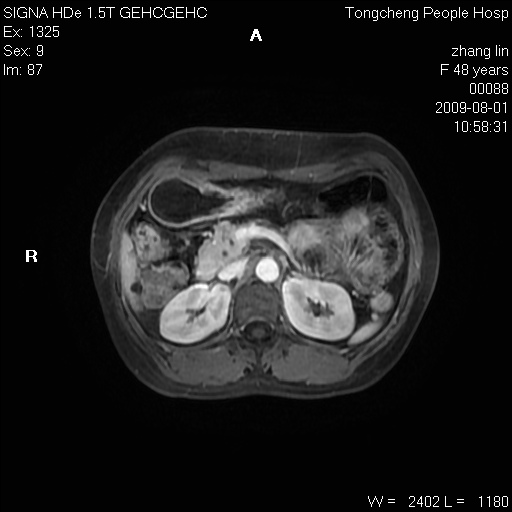

女,48岁。健康体检,彩超发现右肾占位性病变。平素健康。

临床诊断:右肾占位性病变,性质待定(囊肿?肿瘤?)。

上中腹部mr平扫+增强扫描,图像如下:

右肾上极见一类圆形病灶,t1wi呈等信号t2wi呈等高混杂信号,三期增强无强化,边界清---考虑囊肿出血。

同反相位均表现为等信号,病变无强化,考虑含蛋白的囊肿可能,弥散加权相或许有些帮助,

肝囊肿

慢性胆囊炎